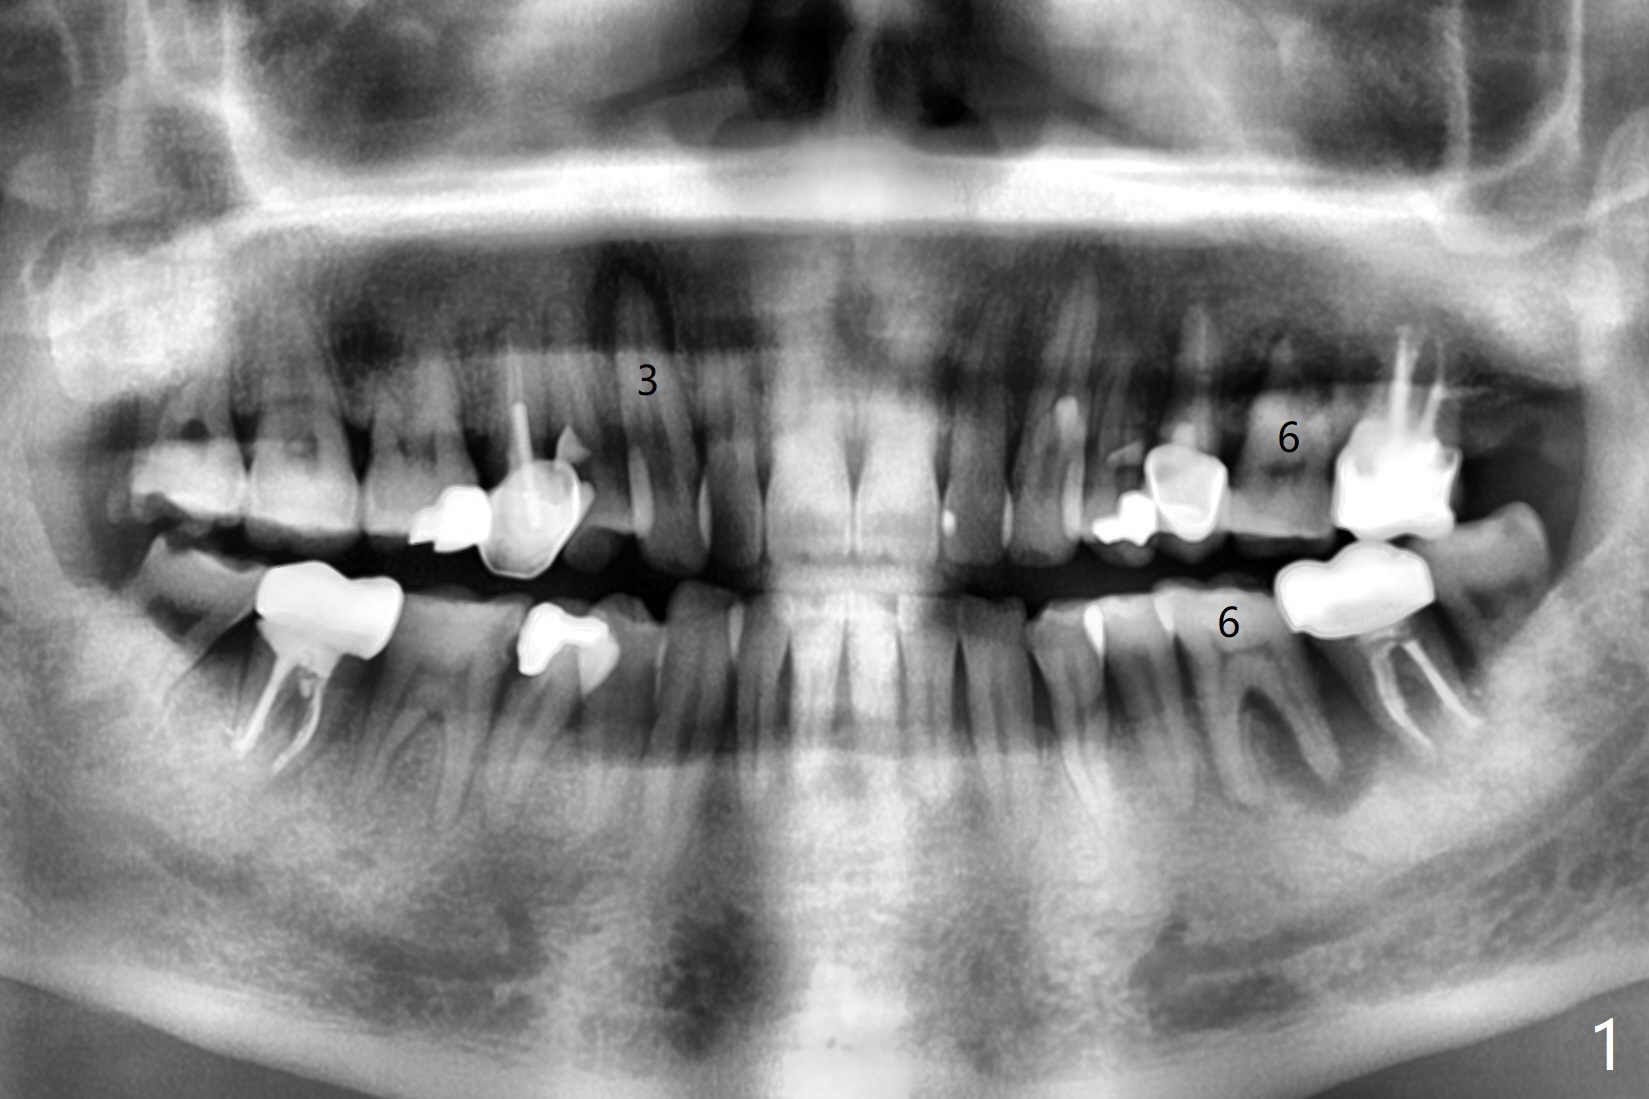

54岁男牙齿问题好像与牙周病和咀嚼力大有关(图一),虽然右上3(图二)和左下6(图三,四)需要治疗,因为疼痛他要求先处理左上6(图五)。后者腭侧根骨质吸收严重,植体尽量颊侧植入(图六),4.5 或者5.0x11毫米。放置粘性骨粉至植体平台,为了简化术中基台放置,使用Non-Hex Temporary Abutment,临时牙冠做的尽量大,占据牙槽窝空间,最后将PRF膜塞入两者之间。Return to Prevent Molar Periimplantitis (Protocols, Table) No Deviation No Caries Metronidazole CT/前牙植牙 Socket Shield Xin Wei, DDS, PhD, MS 1st edition 10/11/2020, last revision 02/21/2021